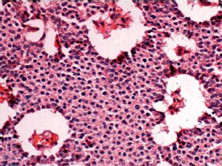

胰岛素瘤(lusulinoma)为胰岛B细胞肿瘤,又称内源性高胰岛素血症,是器质...